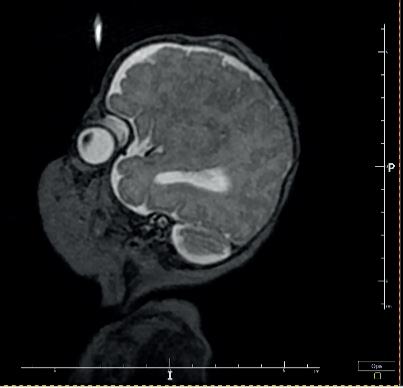

Kolejną interesującą publikacją jest artykuł Studium przypadku zespołu mozaikowej trisomii chromosomu 9 prof. Lidii Perenc z Instytutu Nauk o Zdrowiu Uniwersytetu Rzeszowskiego i współautorów. Zespół mozaiki trisomii 9 został opisany w 1973 roku przez amerykańskiego genetyka R. Haslama; w aktualnych danych uzyskanych z portalu orpha.net zaliczany jest do chorób rzadkich. W artykule omówiono przypadek kliniczny mozaikowej trisomii chromosomu 9 u niemowlęcia płci męskiej. Autorzy wskazują, że dla ustalenia prawidłowego rozpoznania należy uporządkować dane uzyskane na podstawie wywiadu, badania przedmiotowego i badań dodatkowych. W przypadku podejrzenia nieprawidłowego genotypu jako czynnika etiologicznego należy wykonać odpowiednie badania genetyczne. Warto również porównać obraz kliniczny i historię choroby pacjenta z danymi przedstawionymi w literaturze.

Another interesting publication is the article Case study of mosaic trisomy 9 syndrome by Professor Lidia Perenc from the Institute of Health Sciences at the University of Rzeszów and co-authors. Mosaic trisomy 9 syndrome was described in 1973 by American geneticist R. Haslam, and is classified as a rare disease in current data obtained from the orpha. net portal. This article discusses a clinical case of mosaic trisomy 9 in a male infant. The authors point out that in order to establish a correct diagnosis, the data obtained from the history, physical examination and additional investigations should be sorted out. If an abnormal genotype is suspected as an aetiological factor, appropriate genetic tests should be performed. It is also worth comparing the patient’s clinical picture and medical history with data presented in the literature.